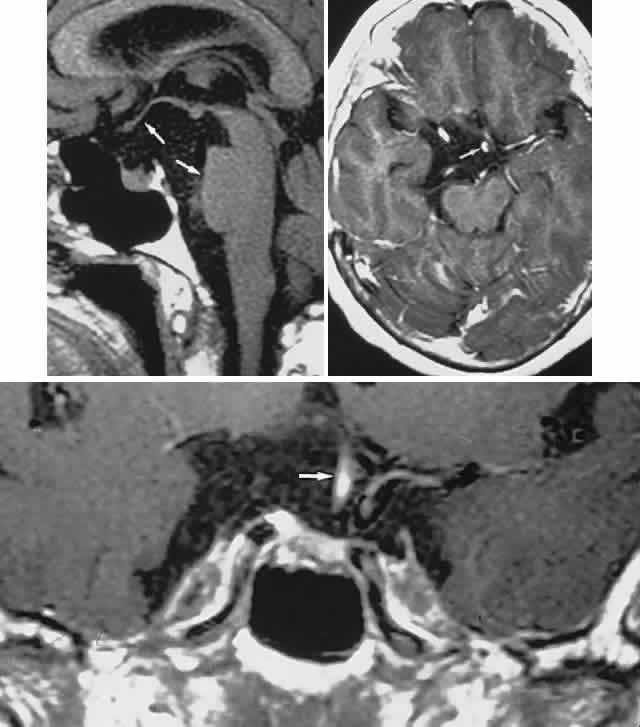

The absence of field defects, for example, in patients undergoing evaluation for amenorrhea, galactorrhea, or sellar enlargement incidentally discovered, does not imply the absence of an adenoma. Obviously, patients with microadenomas, that is, confined within the sella, do not have field defects. From a study24 of 50 cases of pituitary adenomas with chiasmal syndrome, it was concluded that visual disturbance occurs when the chiasm is displaced approximately 10 mm upward (see also Volume 2, Chapter 4, Fig. 6). The modern management of pituitary adenomas should involve several disciplines: current neuroradiologic studies detect microadenomas and provide precise delineation of gross morphology and status of neighboring structures, and mixed MRI signals suggest new or old hemorrhage, cysts, and so forth (Fig. 2); radioimmunoassay techniques assay PRL and other endocrine levels; oral neuropharmacologic agents, such as bromergocryptine, provide a “medical adenomectomy” for hyperprolactinemia and acromegaly; transsphenoidal surgery, including high-illumination microscopical procedures, televised radiofluoroscopic monitoring, and infection control, has all but replaced transcranial approaches; immunohistochemistry techniques have replaced the anachronistic tinctorial designations (e.g., chromophobe, basophilic) with a functional classification.

Fig. 2. Large prolactinoma. Original vision in the right eye (RE) was 8/200, left eye (LE) 1/200, with serum prolactin of 26,000 ng/ml and galactorrhea. Four months of bromocriptine reduced prolactin to 661 ng/ml, vision improved to RE 20/40, LE 20/50. At 3 years, vision was as follows: RE 20/30, LE 20/20; prolactin was 25.9 ng/ml. Enhanced magnetic resonance imaging. Sagittal (A) and coronal (C) images at diagnosis. Sagittal (B) and coronal (D) images at 2-year follow-up, showing dramatic shrinkage of the mass.